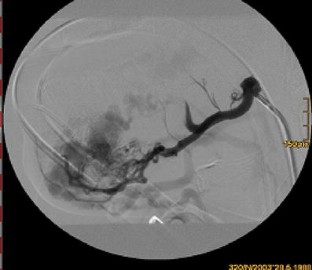

Arteriovenous malformation (AVM) of the mandible is not only a rare entity, but also one that can be potentially life threatening due to massive haemorrhage. The authors describe three cases of children with AVM of the mandible.

Sakkas, N., Schramm, A., Metzger, M.C. et al. Arteriovenous malformation of the mandible: a life-threatening situation. Ann Hematol 86, 409–413 (2007). https://doi.org/10.1007/s00277-007-0261-2